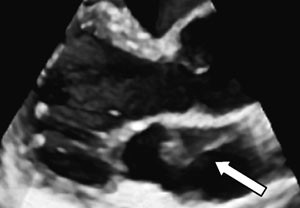

Som ledd i utredningen ble det utført transtorakal todimensjonal ekkokardiografi, som viste normale forhold, bortsett fra en mulig membran i venstre atrium som delte atriet inn i ett bakre og ett fremre kammer (fig 2).

Ved funn av membraner i venstre atrium er det viktig å bestemme de anatomiske forholdene for å kunne stille riktig diagnose. Differensialdiagnostisk er det særlig viktig å avgjøre relasjonen til aurikkelen. En supravalvulær mitralring er lokalisert apikalt for aurikkelen, mens en atriemembran (også kalt cor triatriatum sinister) er lokalisert basalt for denne. Venstre atrie-membran er en sjelden medfødt hjertefeil der en membran deler venstre atrium i to: Ett bakre kammer, som tar imot blod fra lungevenene, og ett fremre kammer, som kommuniserer med aurikkelen og venstre ventrikkel over mitralklaffen (2). Membranen er sannsynligvis et resultat av manglende resorpsjon av den felles lungevenen. En liknende tilstand kan forekomme i høyre atrium (3).

Transtorakal ekkokardiografi var ikke tilstrekkelig til å stille en sikker diagnose. Vi valgte derfor å gå videre med transøsofageal ekkokardiografi, som viste at membranen dekket en relativt stor del av atriet (fig 3). Det så ut til å være god passasje for blodstrømmen, siden det ikke var tegn til utvidelse av atriet proksimalt for membranen. Det var heller ikke andre tegn til obstruksjon, som tåkevirvler i den bakre del av atriet eller retrograd blodstrøm i lungevenene. Membranen var lokalisert basalt for aurikkelen. Det dreide seg dermed om en venstre atrie-membran.

Den transøsofageale undersøkelsen har betydelige fordeler fremfor den transtorakale når det gjelder strukturer i atriene, pga. av fysiske begrensninger ved ultralydteknologien. Hos denne pasienten kunne transøsofageal ekkokardiografi bekrefte diagnosen og belyse betydningen av membranen for blodstrømmen.